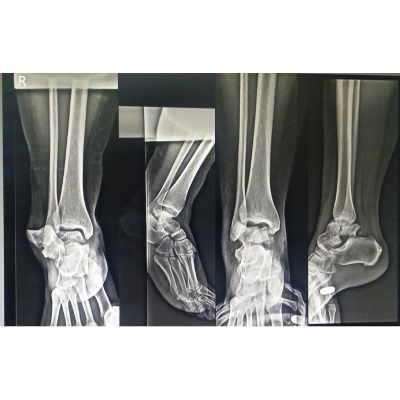

Cavus Foot की सर्जरी के बाद, मरीज अब आराम से चल पा रहा है।

Equino-Cavo-Varus is a complex foot deformity involving high arches, inward heel turning, and toe pointing. Treatment often includes surgery, bracing, or physiotherapy to restore proper alignment and function.